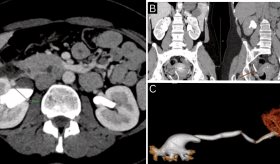

El objetivo principal fue reducir el volumen tumoral y mejorar la calidad de vida del paciente, permitiendo el drenaje adecuado de la vía biliar obstruida.

"Utilizamos un dispositivo que es el Habib EndoHPB Bipolar Radiofrequency Catheter que lo que permite es hacer una necrosis del tumor, es un catéter de ablación que actúa con calor, y lo que hace es obstruir el drenaje biliar mediante este catéter lo que nosotros hacemos es quemar el tumor.

De esta forma, se abre un túnel en la obstrucción, para que el drenaje biliar continúe como de costumbre, esto les da mejor calidad de vida, y aunque probablemente no se pueda desaparecer el tumor, ya que esta intervención se hace de manera paliativa, en pacientes que ya han sido sometidos a unos tratamientos convencionales.

"Logramos impermeabilizar el ducto biliar de este paciente, ya le habíamos hecho intervenciones previas y el tumor estaba creciendo y estaba generando obstrucción del drenaje biliar, y con con los resultados obtenidos con la ablación, logramos abrir un espacio a ese drenaje normal que debe tener el ducto biliar y mejorar drenaje hepático." explicó.